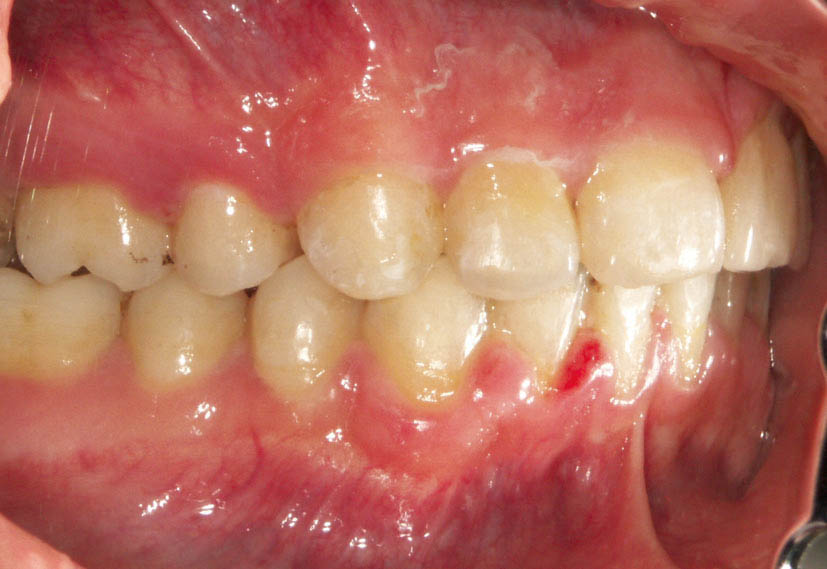

شکل 110-2: اکلوژن 5mm کلاسII

شکل 111-2: نتیجه درمان یک کاسپ کامل کلاسII تمام میشود.